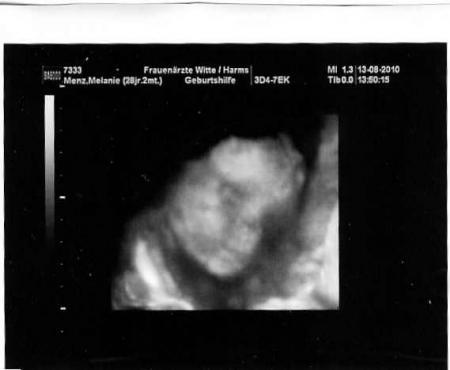

Vielleicht klappt es ja nu mal mit einem Bild...

Bild zu